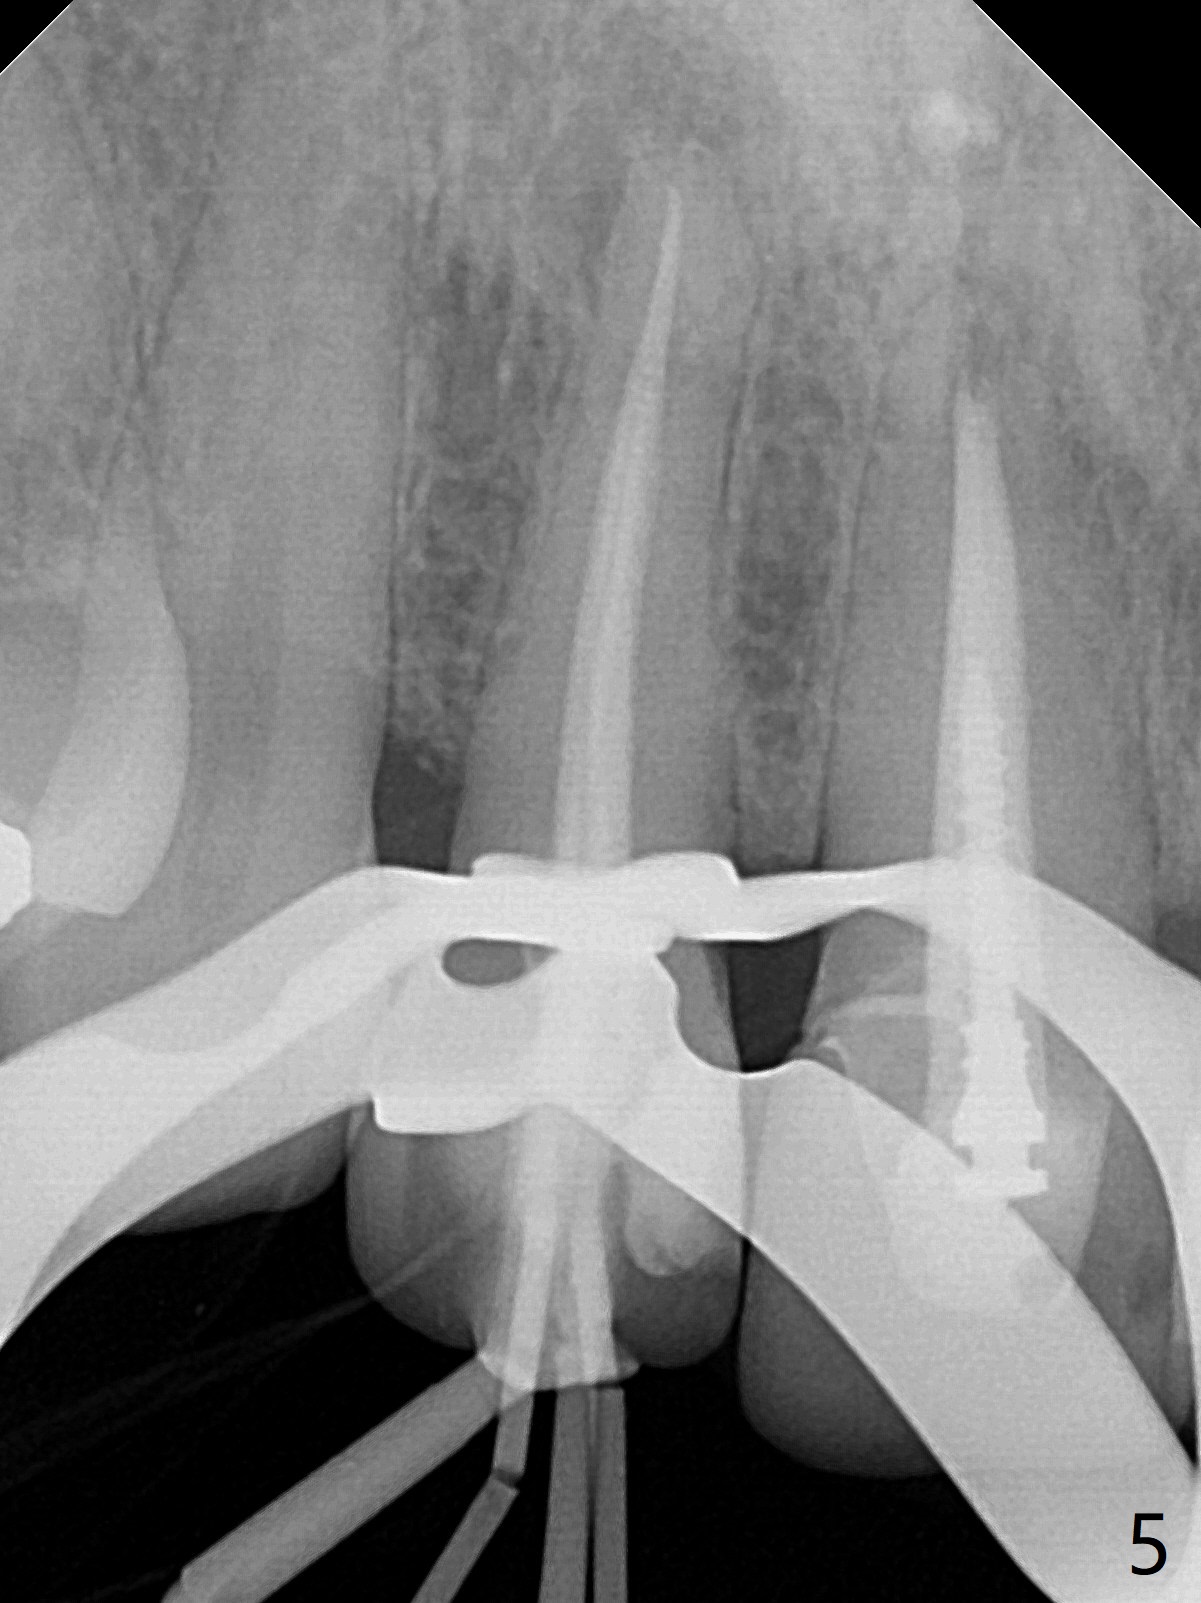

A 46-year-old woman requests a crown for the discolored tooth #7 (Fig.1,2) with mesiolingual composite (Fig.3 C) and periapical radiolucency (*). After RCT (Fig.4,5) with sodium hypochlorite, the tooth #7 is whiter than the ML composite (Fig.6,7). The patient returns 1 day post RCT for in house internal and external bleaching (Fig.8) with 35% hydrogen peroxide gel closed in the canal when she leaves. Three weeks later, the lateral incisor has the shade as the neighboring natural teeth (Fig.9,10). After the lightest shade composite placed in the canal and the access hole (Fig.11), the lateral looks better than the central with a crown and cervical discoloration (Fig.12).